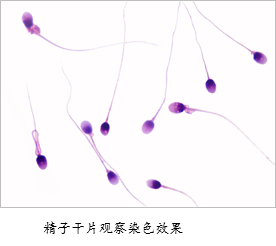

精子形态检查是将液化后的精液涂片后染色,在显微镜下观察精子的形态特征,计算正常形态精子的百分率。主要用于男性不育症的诊断。[查看详细] 精子形态正常值: 正常形态

简介:精子形态分析是指通过涂片染色的研究方法,观察与分析精子形态,了解正常精子与生理及病理范围内的变异精

简介:精子形态检查是将液化后的精液涂片后染色,在显微镜下观察精子的形态特征,计算正常形态精子的百分率。主要用